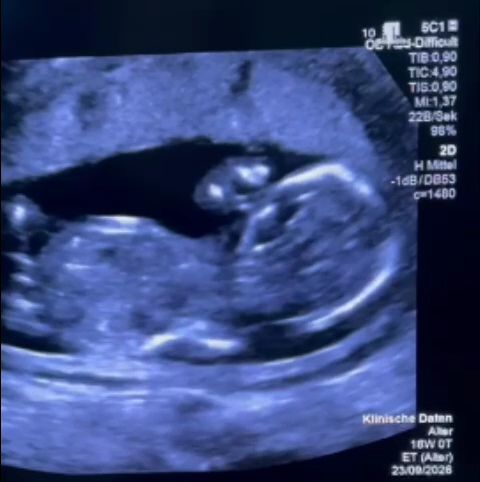

O gravidă din România, confruntată cu o malformație minoră a fătului, a trecut printr-o experiență traumatizantă la un spital din București, fiind lipsită de informații și refuzată în demersul de a beneficia de tratament. Povestea a fost relatată de MONICA Althamer, fost secretar de stat în Ministerul Sănătății și director de program în cadrul Fundației Metropolis. Pacienta, aflată în săptămâna a 12-a de sarcină, a descoperit malformația, pentru care exista un tratament, dar a fost întâmpinată cu incompetență și indiferență din partea personalului medical român.

Părinții, după ce au solicitat informații, au optat pentru a efectua tratamentul la Spitalul Filantropia din București. Aici, însă, au avut parte de un tratament degradant. Nu au primit informațiile necesare, iar personalul medical le-a sugerat să aștepte, în ciuda faptului că un medic german a recomandat intervenția urgentă. Când au cerut documente pentru a putea beneficia de tratament gratuit în străinătate, au fost refuzați, conform declarațiilor.

Situația a culminat cu o experiență neplăcută, care a dus la necesitatea ca tratamentul să fie realizat în Germania. Cuplul a fost constrâns să caute soluții alternative, depășind limitele sistemului medical românesc. În cele din urmă, procedura a fost efectuată la o clinică din Germania, unde un specialist german a calificat consilierea primită în România drept „extrem de slabă”. Această afirmație subliniază diferențele majore în abordarea medicală și în calitatea serviciilor oferite.

Demersurile pentru obținerea documentelor necesare tratamentului în străinătate au eșuat. Această lipsă de sprijin a forțat părinții să caute soluții în afara țării. Decizia de a căuta ajutor în Germania a demonstrat lipsa de opțiuni și încredere în sistemul medical autohton. La scurt timp după Paștele Catolic, cuplul a ajuns în Germania, iar procedura medicală a fost efectuată cu succes de către un medic specialist.